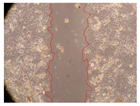

2.2. Evaluation of the In Vitro Wound-Healing Activity

| Representative Image of the Cells at the Initial Moment (0 h) | ||||

| 2 h | 8 h | 12 h | 24 h | |

| Control | ![]() | ![]() | ![]() | ![]() |